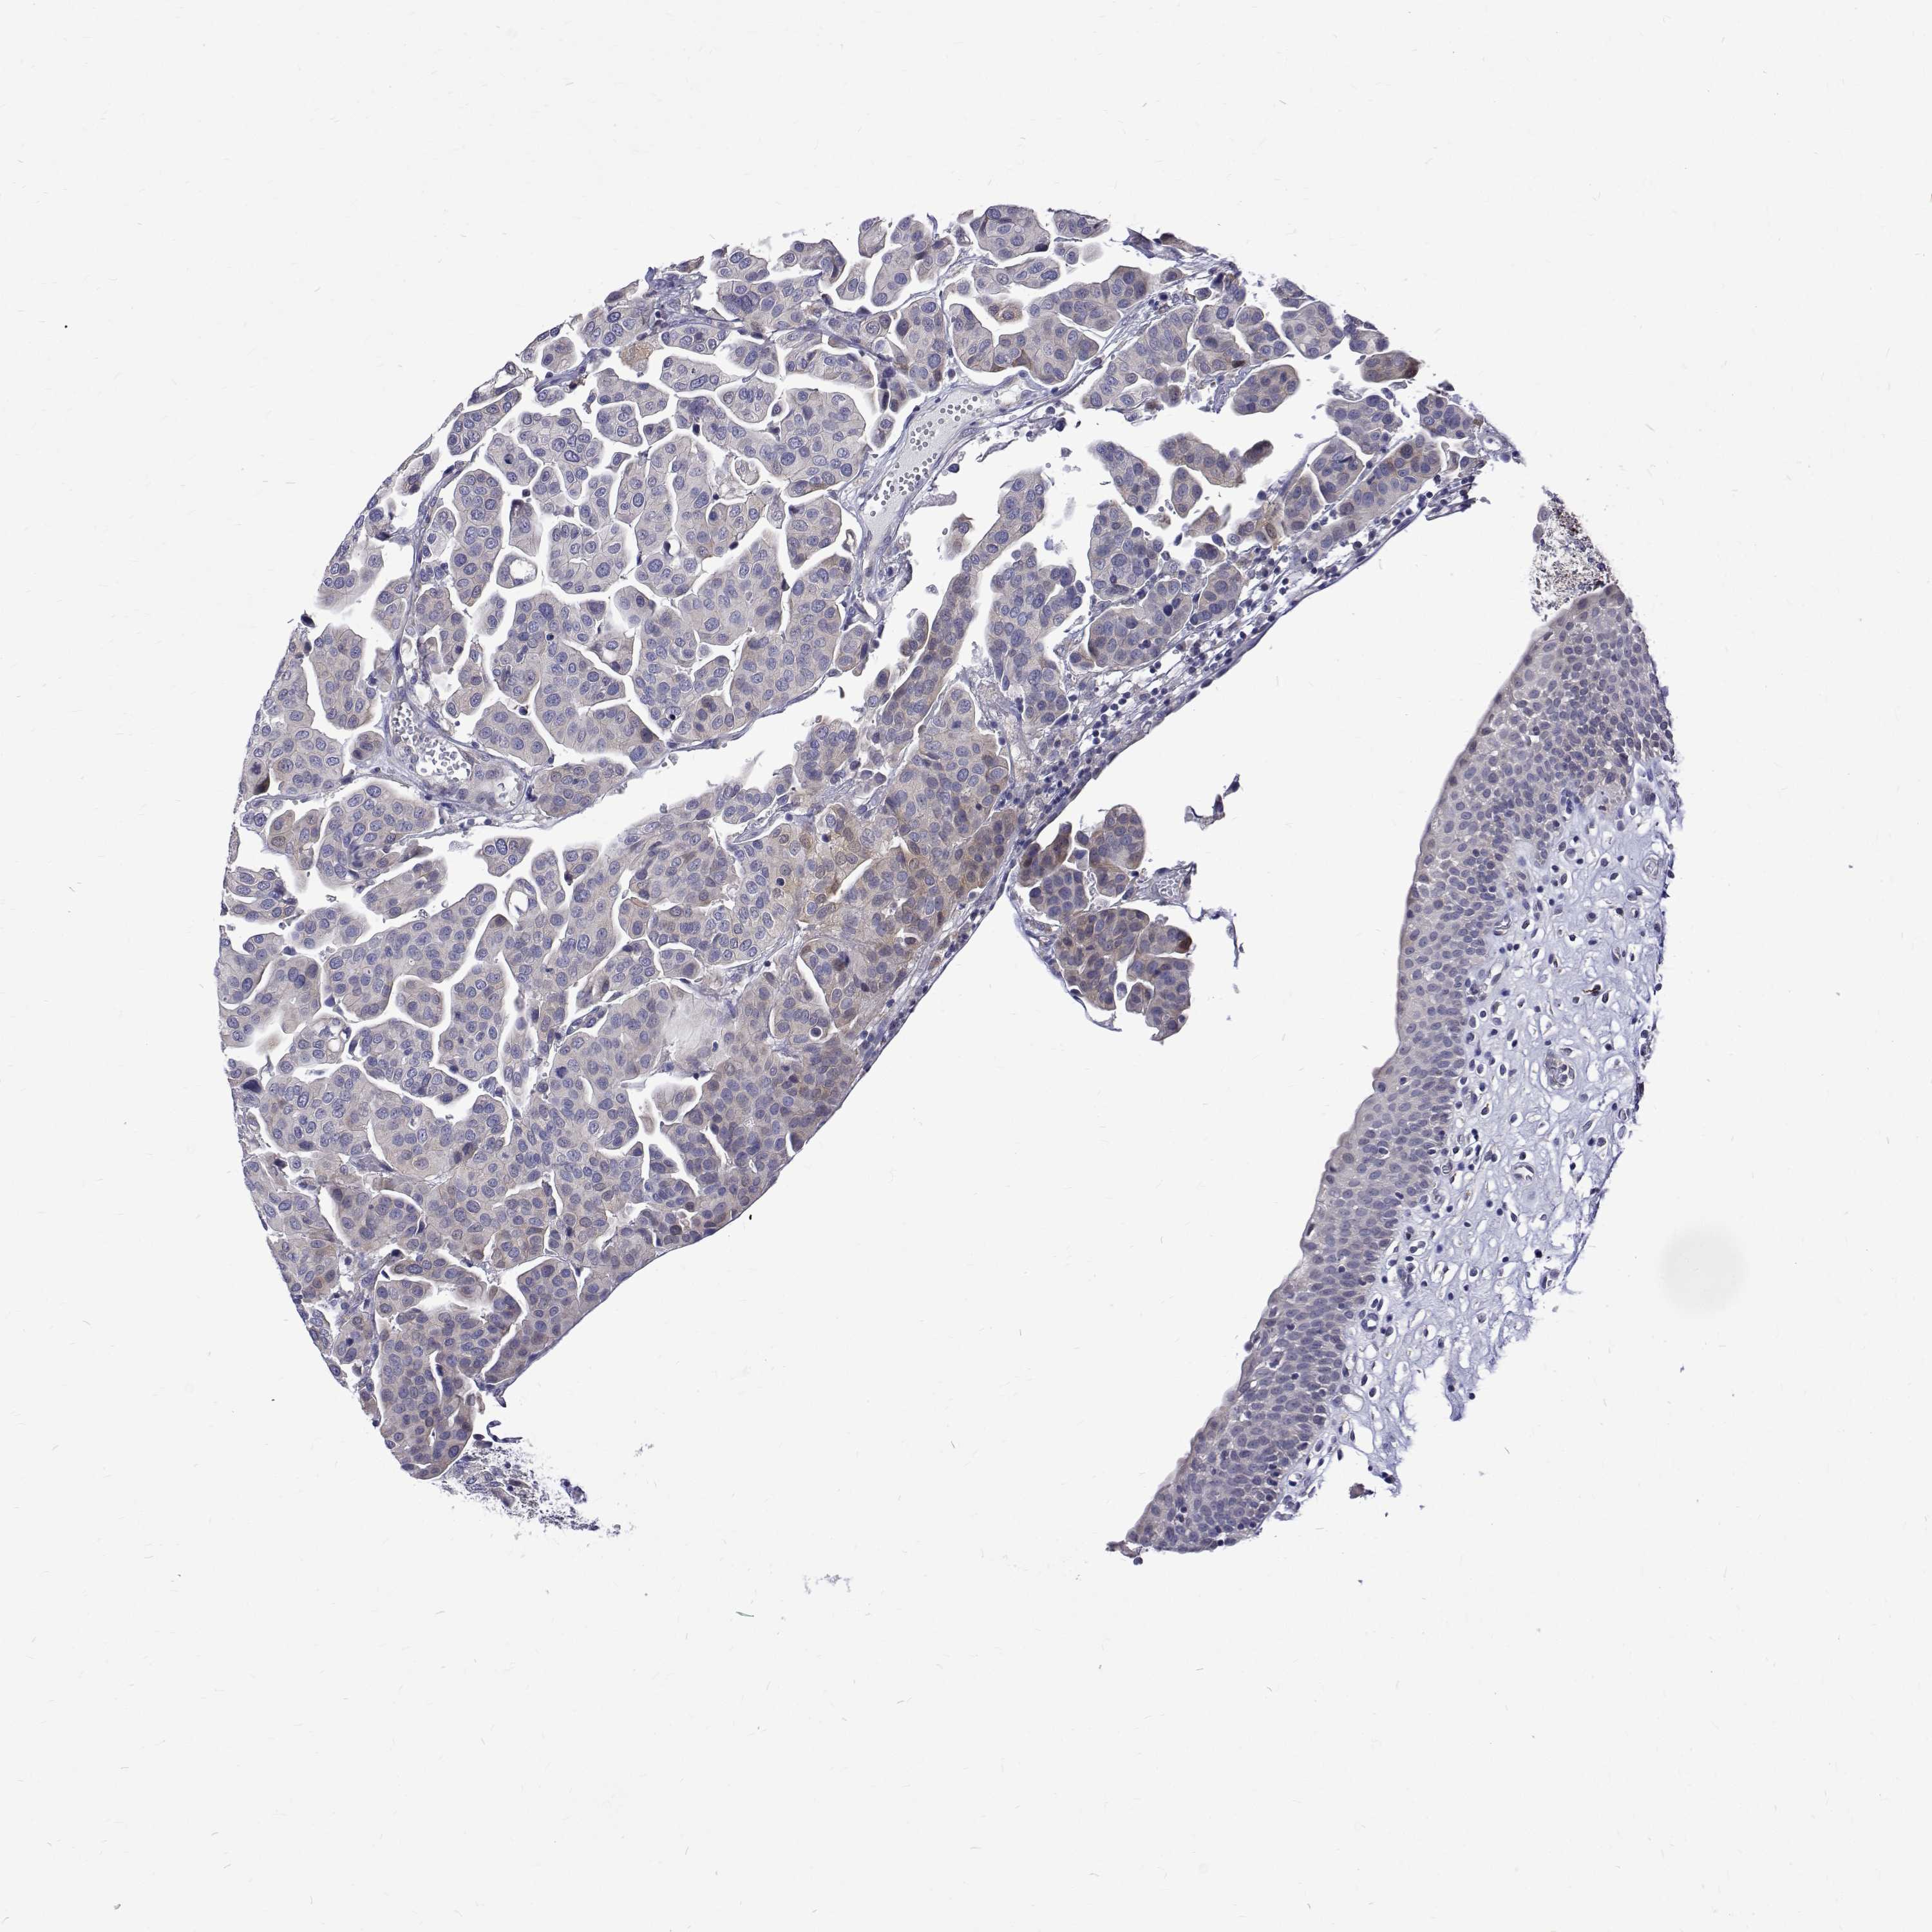

KIDNEY RENAL CLEAR CELL CARCINOMA (TCGA) - Interactive survival scatter ploti

The Survival Scatter plot shows the clinical status (i.e. dead or alive) for all individuals in the patient cohort, based on the same data that underlies the corresponding Kaplan-Meier plots. Patients that are alive at last time for follow-up are shown in blue and patients who have died during the study are shown in red.

The x-axis shows the expression levels (FPKM) of the investigated gene in the tumor tissue at the time of diagnosis. The y-axis shows the follow-up time after diagnosis (years). Both axes are complimented with kernel density curves demonstrating the data density over the axes. The top density plot shows the expression levels (FPKM) distribution among dead (red) and alive patients (blue). The right density plot shows the data density of the survived years of dead patients with high and low expression levels respectively, stratified using the cutoff indicated by the vertical dashed line through the Survival Scatter plot. This cutoff is automatically defined based on the FPKM cutoff that minimizes the p-score. The cutoff can be changed by dragging the vertical line or by entering a cutoff value in the square labeled "Current cut-off".

Under the Survival Scatter plot the p-score landscape (black curve; left axis) is shown together with dead median separation (red curve; right axis). Dead median separation is the difference in median mRNA expression between patients who have died with high and low expression, respectively. It is calculated as follows: median FPKM expression of dead patients with high expression - median FPKM expression of dead patients with low expression. This is intended to aid the user in visually exploring custom cutoffs and the associated p-scores and dead median separation.

Individual patient data is displayed and can be filtered by clicking on one or more of the category buttons on the top of the page. Categories describing expression level and patient information include: high, low, alive, dead, female, male and tumor stages. The scale of the x-axis can be toggled between linear and log-scale by clicking on the "x log" button. Mouse-over function shows TCGA ID, patient information and mRNA expression (FPKM) for each patient.

& Survival analysisi

Kaplan-Meier plots summarize results from analysis of correlation between mRNA expression level and patient survival. Patients were divided based on level of expression into one of the two groups "low" (under cut off) or "high" (over cut off). X-axis shows time for survival (years) and y-axis shows the probability of survival, where 1.0 corresponds to 100 percent.

PADI1 is not prognostic in Kidney Renal Clear Cell Carcinoma (TCGA)

Best expression cut offi

Based on the FPKM value of each gene, patients were classified into two groups and association between prognosis (survival) and gene expression (FPKM) was examined. The best expression cut-off refers the FPKM value that yields maximal difference with regard to survival between the two groups at the lowest log-rank P-value. Best expression cut-off was selected based on survival analysis .

When clicking on this number, the vertical dashed line indicating cut-off, the interactive survival plot, and the Kaplan-Meier curve will be adjusted to show results based on the best expression cut-off.

: 0.05

TCGA RNA samplesi

RNA-seq data is reported as average FPKM (number Fragments Per Kilobase of exon per Million reads), generated by the The Cancer Genome Atlas (TCGA) .

Normal distribution across the dataset is visualized with box plots, shown as median and 25th and 75th percentiles. Points are displayed as outliers if they are above or below 1.5 times the interquartile range. FPKM values of the individual samples are presented next to the box plot.

Average pTPM 1.6

Number of samples 521